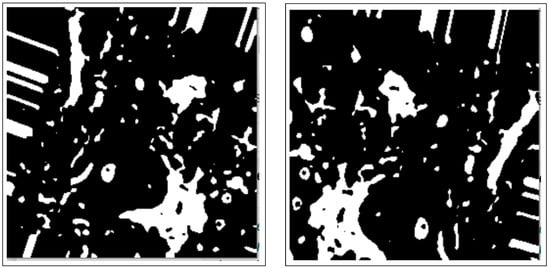

- Morphology operations enhance the image by highlighting important features. The connected components analysis method is used to group components with similar characteristics and assist in separating overlapping and non-overlapping objects.

3.2.2. Morphology Operations

3.3.1. Connected Components Analysis

3.3.2. Active Contours Segmentation